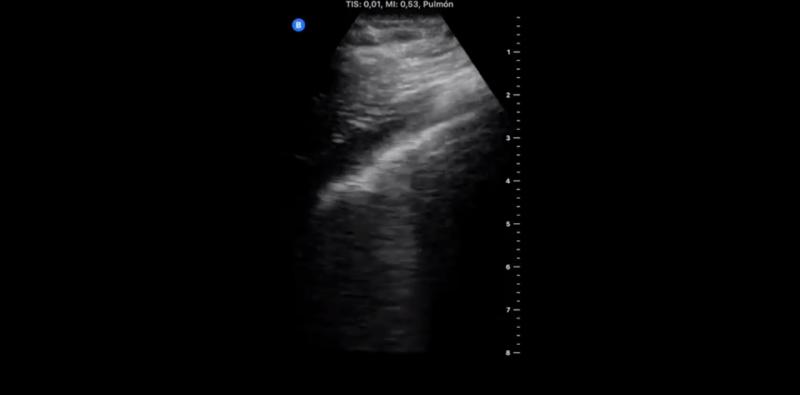

În cea de-a doua zi de autoizolare, medicul a scris: „Ziua 2 după ce am fost diagnosticat cu COVID-19. Durere mai slabă în gât, tuse și durere de cap, fără dificultăți respiratorii sau durere în piept”. Însă, medicul a precizat că a început să observe schimbări în plămânii săi, precum linia pleurală îngroșată.

Plămânii doctorului Yale Tung Chen, în a doua zi după diagnosticul COVID-19.